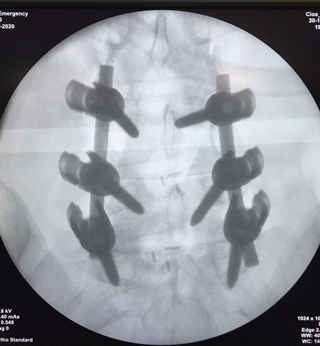

手术中可扩张通道辅助系统显示范围及减压固定的X片